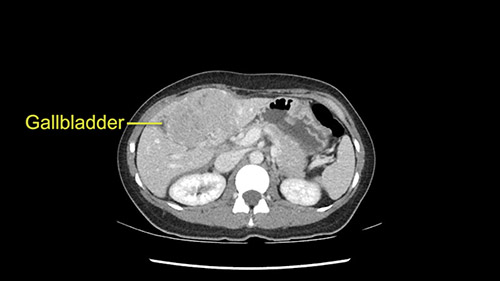

When you see the axial sections of the scan, you find it's a largely exophytic mass and its well-encapsulated. So this is typically true of a well-differentiated hepatocellular carcinoma. If you look at this, this is the gallbladder which is being displaced to the right and the mass is in the Sg4 of the liver, exophytic, projecting down. As it is coming down, it is also displacing the duodenum and the head of the pancreas which is being pushed towards the left and it's going right up to the cava, the start of the anterior surface of the cava. Obviously getting a lot of collaterals and vascularity from all the vessels around but one has to be very careful in evaluation of the main portal pedicle in this particular case and of course arterial inflow to the Sg4 and of course the left lobe of the liver.

The next step would be to carefully palpate and make sure that this adherence to any vascular structures is not there. I would start off by slowly mobilizing it from the duodenum inferiorly and lift the tumor up and expose the portal pedicle on the top. The portal pedicle and the hepatic arterial system has to be carefully traced. I want you to really slow down at this point of time and anatomically identify each of the vascular structures we are mentioning right now. Where is the proper hepatic artery, and where is the branching into the left and right hepatic arteries. Many times a left hepatic artery is given off early which is good for us and also when you go up on to the hilum, you find that the gallbladder is very close and adherent to the tumor so one has to work on the plane of the common bile duct, identify the cystic duct, ligate the cystic duct, and perhaps even leave the gallbladder on to the tumor and not try and dissect it from the tumor because the plane of transection will be at the Cantlie’s line which is the gallbladder fossa. Once you do this, then you go up and you need to take the portal bifurcation from below and of course the arterial supply to the segment which we are resecting.

So in planning for this operation, as I look at the scans, I first visualize the arterial phase and I can see that there’s are a lot of big feeding arteries to this large tumor. Likely all the right side vessels feeding the right side of the liver: right hepatic artery and likely the Segment 4 artery are spared from the tumor. It’s likely the left hepatic artery is ramificating and giving feeding arteries to this tumor. It certainly looks like a large mass that its compressing other structures like the cava, the pancreas, the stomach; but I think there’s a plane and we can see that better in the venous phase. There’s a plane of separation between the gallbladder, the pancreas, the cava, that this tumor is abrupting but likely not invading. Usually, these masses actually don’t invade at that level and basically are pushing the tissues and once you open, you’re able to separate the tumor. Sometimes there’s some adhesions but you can actually separate and there’s usually no invasion.